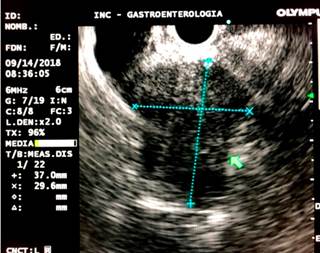

Based on these findings, palliative care was decided by performing a biliary stent placement by means of an ERCP. During the procedure, the papilla was found to be distorted with local retraction of the duodenal walls, and despite cannulation of the distal bile duct was achieved, cannulation of the proximal bile duct was unsuccessful. EUS-guided biliodigestive shunt was then performed, in which a neoplastic infiltration of the duodenal papilla preventing its cannulation and a 23 mm heterogeneous hypoechoic lesion in the head of the pancreas with an up to 18 mm retrograde bile duct dilation were found (Figure 4). An initial puncture of the mass was performed for histological study purposes and then of the transduodenal bile duct with a 19 Fr. needle, which allowed the advancement of the 0.035” hydrophilic guide wire; dilatation was achieved using a biliary balloon dilator under fluoroscopic control and subsequent placement of the 10 x 80 mm fully covered metal stent was performed, which was released under endoscopic and fluoroscopic control achieving adequate opening and drainage of the contrast medium and clear bile, without subsequent complications (Figures 5 and 6). The cytology report of the samples obtained through endosonography confirmed adenocarcinoma involvement. Two months later, a total bilirubin control was performed obtaining the following results: total bilirubin: 2.42 mg/dL; direct bilirubin: 1.85 mg/dL, and indirect bilirubin: 0.58 mg/dL (Figure 7). Palliative care was continued in the oncology service.

Figure 5 Endoscopic-guided bile duct cannulation and fluoroscopy in which dilatation with distal amputation is observed.